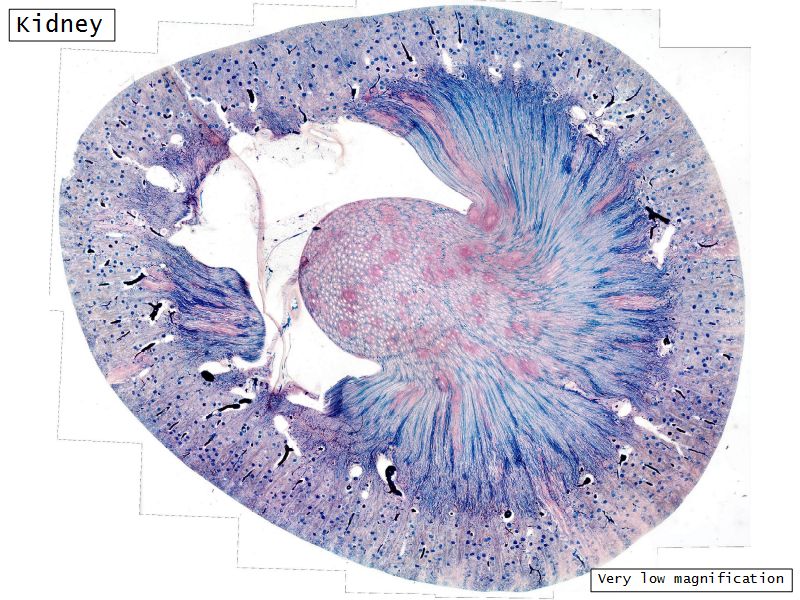

- Complete the drawings for each slide in the practical workbook.

Kidney

- Capsule

- Cortex

- Medulla

- Multilobar

Multilobar

Appearance

- Cortex

- Renal corpuscles

- Convoluted tubules

- Medulla

- Loops of Henle

- Collecting tubules

Kidney lobule

- Group of neprons

- Open into branches

- Same collecting duct

- Not clearly demarcated

- Interlobular arteries/veins